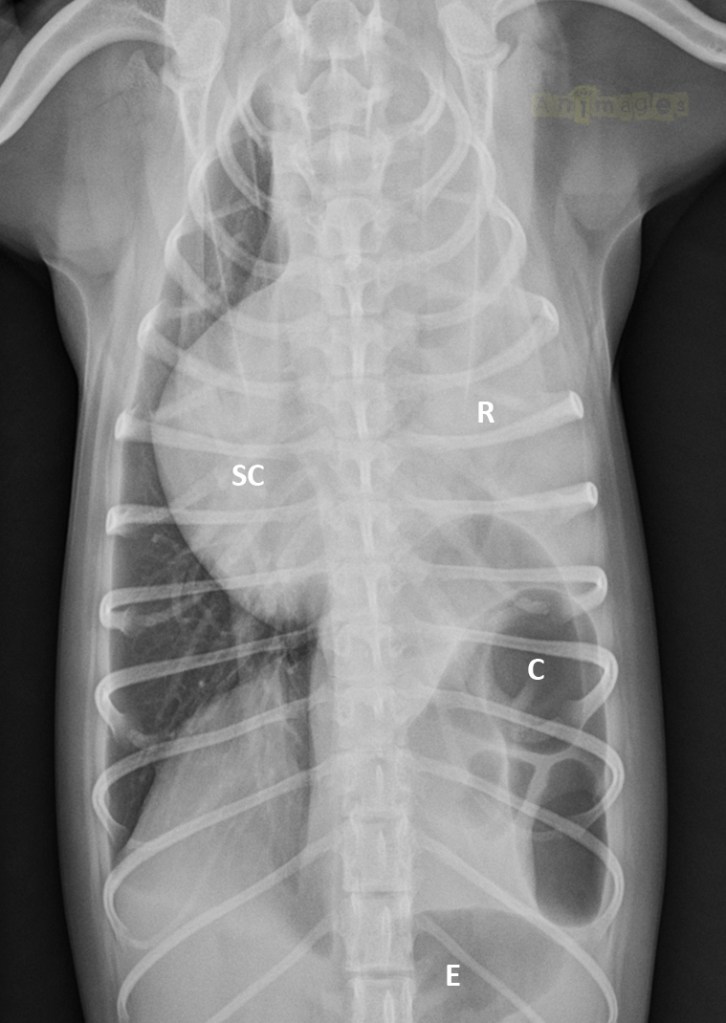

VD-annot